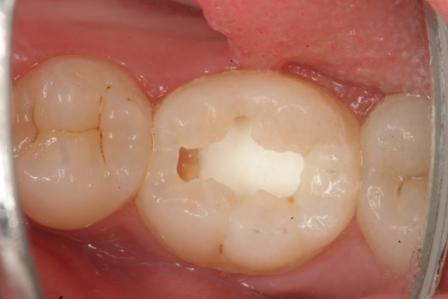

下顎7番の頬側歯茎部カリエスの原因 2025.06.04